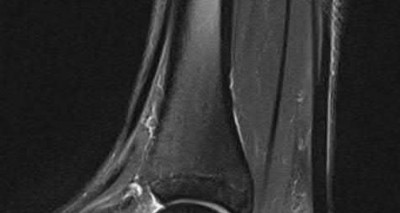

A 38-year-old male suffers the injury shown in Figure A. During operative fixation, free osteoarticular fragments are encountered and reconstruction of these pieces is attempted. Postoperatively, which of the following will have the most beneficial effect on the healing potential of the surviving chondrocytes within these reconstructed articular segments?

Figure A demonstrates a comminuted tibial plateau fracture with significant intra-articular involvement. Basic science evidence has demonstrated that post-operative gentle compressive loading may have a positive impact on articular cartilage healing; however, excessive shear loading may be detrimental.

Irrgang et al provide guidelines for rehabilitation following surgical management of articular cartilage lesions of the knee. They state that after articular cartilage repair, exercises to enhance muscle function must be done in a manner which minimizes shear loading of the joint surfaces in the area of the lesion. The authors also discuss the benefits of gentle compressive loading and motion of the joint, and its positive effects on chondrocyte nutrition.

Furthermore, they recommend a period of protected weight bearing as often being necessary, and that this should be followed by progressive loading of the joint.